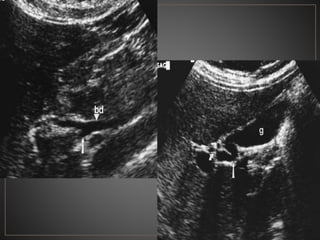

CPRE: Dilataciones saculares de CBIH. TC: Simple:Áreas redondas, hipointensas en topografía de CBIH. Contraste: Signo del punteado central. RM: T2: Espacios quísticos hiperdensos

• #52 USG en escala de grises donde se observa una dilatación de los conductos biliares intrahepaticos, con el signo del punteado central, a la aplicacion de doppler color se percibe flujo en las venas portales.